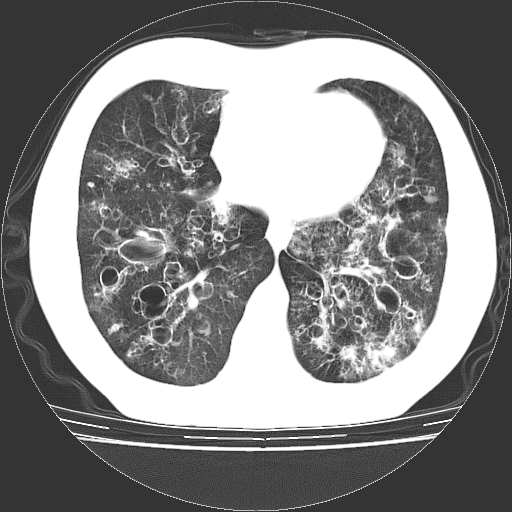

以下是引用zyx168在2006-12-4 15:30:00的发言:[br]经典!支气管肺囊肿并感染。

以下是引用dyqct在2006-12-4 17:11:00的发言:[br]典型的囊状支扩合并感染。

以下是引用liaoqiang在2006-12-4 16:12:00的发言:[br]局部肺叶内可见扩张的支气管壁,考虑为支扩。部份囊样影内有小液平和肺内散布斑片征影、小结节及纤维灶,提示支扩伴感染,且由于局部呈现有树芽征感染以结核可能性大。

以下是引用zhoucan076在2006-12-4 16:48:00的发言:[br]囊状支扩合并感染